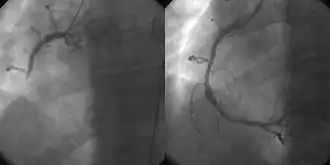

3D Medical Animation still shot of Percutaneous coronary interventionthe use of angioplasty for the treatment of obstruction of coronary arteries as a result of coronary artery disease. A deflated balloon catheter is advanced into the obstructed artery and inflated to relieve the narrowing; certain devices such as coronary stents can be deployed to keep the blood vessel open. Various other procedures can also be performed at the same time. After a heart attack, it can be restricted to the culprit vessel (the one whose obstruction or thrombosis is suspected of causing the event) or complete revascularization; complete revascularization is more efficacious in terms of major adverse cardiac events and all-cause mortality.[4]

PCI is also used in people after other forms of myocardial infarction or unstable angina where there is a high risk of further events. The use of PCI in addition to anti-angina medication in stable angina may reduce the number of patients with angina attacks for up to 3 years following the therapy,[5] but it does not reduce the risk of death, future myocardial infarction, or need for other interventions.[6]